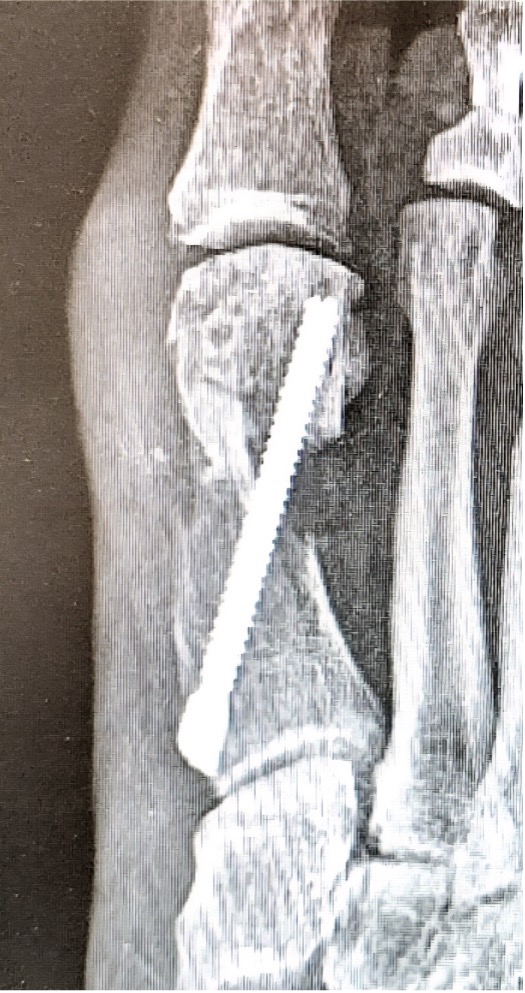

Disengagement of the metatarsal head is another complication discussed in a lecture at the Annual Scientific Conference of the American College of Foot and Ankle Surgeons in Phoenix in 2025.11 It can occur during the first few weeks postop. It is characterized by complete uncoupling of the first metatarsal head (pulling of the screw through the cortex) with complete loss of correction, without failure or movement of the hardware. This complication may or may not be symptomatic, but almost always requires revision (Figures 4 A, B).